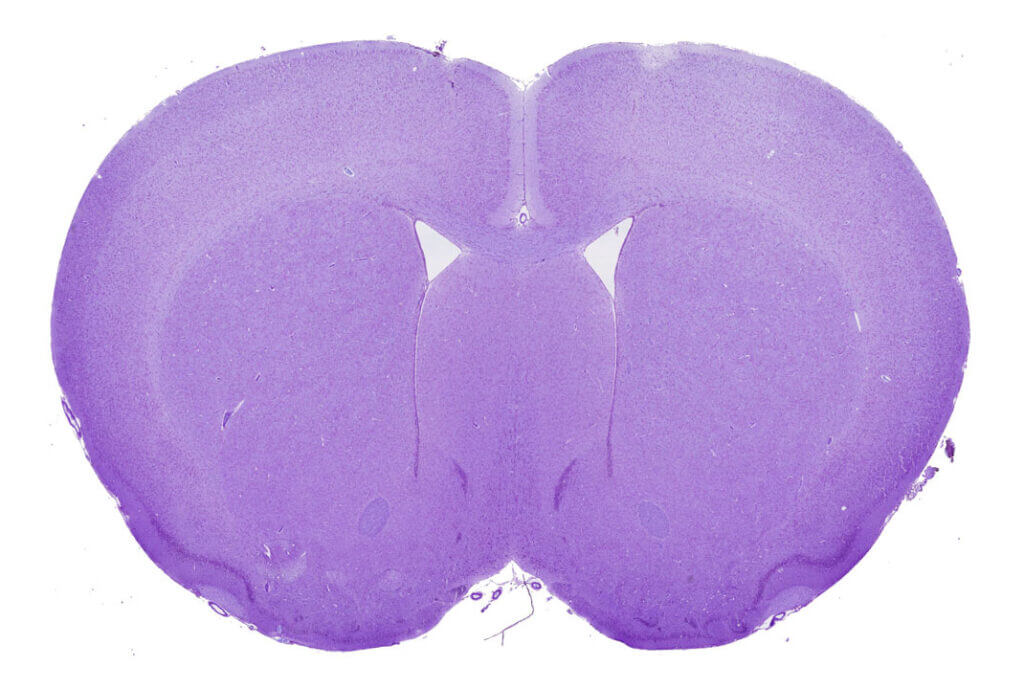

Thromboembolic stroke

MCA occlusion by thrombin injection

This preclinical ischemic stroke model is induced by the formation of a fibrinrich clot in the MCA. This clot is efficiently lysed by standard clinical fibrinolytics (Alteplase, Tenecteplase), reflecting the patient subgroup that responds to standard-of-care fibrinolytics. This makes the model a key translational tool for assessing the efficacy of your thrombolytic candidates. This model is also highly relevant for evaluating neuroprotective compounds in an experimental setting that closely mimics the clinical reality of the acute phase of stroke (with the presence of a thrombus and pharmacological recanalization achieved within a clinically relevant treatment window). It additionally enables the study of interactions with reference fibrinolytic treatments.

MCA occlusion by FeCl₃ or AlCl₃ application

This preclinical ischemic stroke model is induced by the formation of a platelet‑rich clot that is resistant to standard fibrinolytics (Alteplase, Tenecteplase) but responsive to other thrombolytic agents such as N‑acetylcysteine. By reflecting the subpopulation of patients who fail to respond to standard‑of‑care treatments, this translational model is a powerful tool for assessing the efficacy and superiority of your candidates, combination therapies, and pharmacological interactions.

tMCAO model by autologous clot injection

Injecting sizecalibrated autologous blood clots induces embolic occlusion of the proximal MCA segment. This model produces cortical and subcortical lesions similar to those observed in mechanical ischemia models. Mortality, deficit severity, and responsiveness to the reference fibrinolytic treatment (Alteplase) can be modulated by adjusting the amount of thrombotic material used for the embolic event. This original and wellcharacterized model enables the evaluation of a wide range of therapeutic strategies, together with longterm monitoring of functional recovery.

Hemorrhagic stroke

ICH induced by collagenase injection

Stereotaxic injection of collagenase rapidly disrupts the vascular endothelium, inducing a reproducible hemorrhage with the formation of an intracerebral hematoma, accompanied by an inflammatory response and clear neurological deficits. This ICH model provides a valuable translational tool for assessing the efficacy of your drug candidates on bleeding, neuroinflammation, and neuroprotection. Depending on your needs, it also offers the possibility to evaluate the risk of rebleeding or the effectiveness of antidotes across a panel of reference anticoagulants and fibrinolytics.